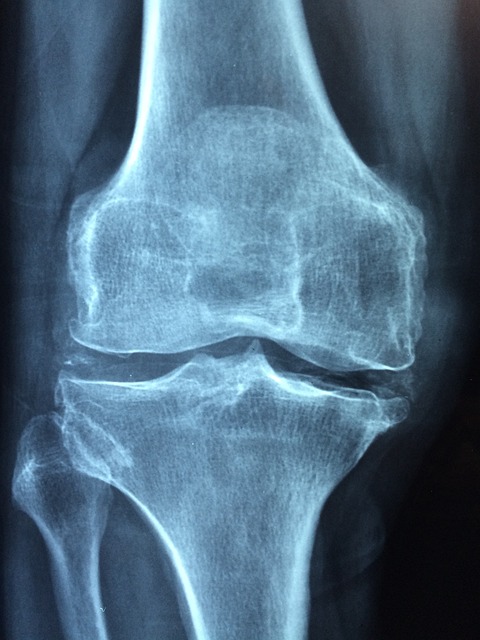

뼈는 단순한 구조물이 아닌 생체 조직으로, 끊임없이 생성과 흡수를 반복합니다.

이 과정에서 조골세포와 파골세포의 균형이 중요한데, MBP는 이 균형을 건강하게 유지시켜 줍니다.